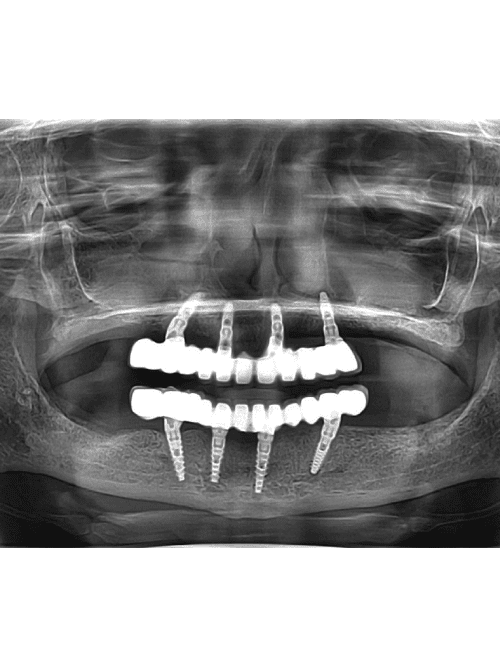

With the innovation of anesthesia dentistry become completely painless. Most dentist uses local anesthesia that numbs the particular area of oral cavity. It can be used in root canal treatment, dental implants fixation, gums surgery, extraction, dental trauma/accident , jaw fracture etc. BEFORE: 1. Always have light meal or breakfast before dentist appointment (for general […]